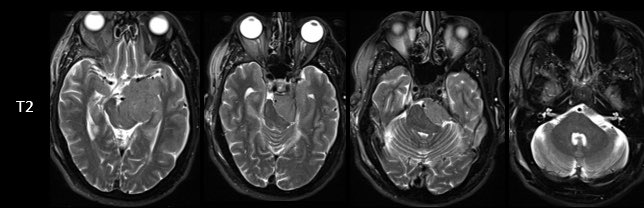

How would you manage this 42F w/ intracranial recurrence of optic nerve sheath meningioma initially biopsied at OSH 5 yrs ago. R eye blind, L 20/20, EOMI. Observation? Radiation? If surgery, approach/extent of resection? #Neurosurgery #MedEd #MedTwitter @EvaWuMD @TheJNS @WFNSHQ